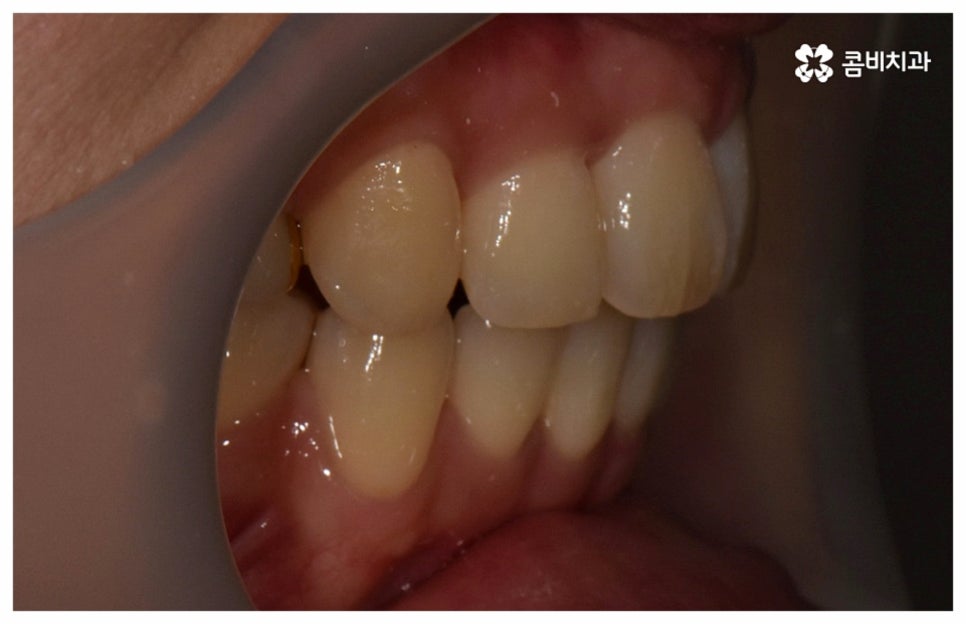

또한 중장년 분들은 젊은 분들에 비해 웃을 때 자연스럽게 윗니보다 아랫니가 더 많이 보이는 경향이 있기 때문에 아름다운 미소에 대해 생각하는 바가 다를 수 있는데요. 이런 경우 만약 치료 후 모습을 미리 예상해서 볼 수 있는 3D 모르페우스 장비가 있다면 상담을 할 때 치료의 목표나 한계에 대해 명확하게 설정하여 환자분들의 만족도를 보다 높일 수 있을 것이므로 치과를 선택하실 때 이런 부분도 잘 체크해 보시길 바라고 있어요.

이와 같이 자연스러운 노화로 인한 변화를 주의깊게 신경쓰면서 충분한 시간을 들여 치아를 이동시키는, 다양한 임상 경험이 풍부한 숙련된 의료진이 처음부터 끝까지 세심하게 케어하는 치과에서 함께 하신다면 중년치아교정 치료를 받는 것을 크게 걱정하실 필요는 없을 거예요. 또한 요즘은 정기 검진 및 스케일링 치료와 같은 평상시 관리의 중요성에 대해 정확하게 인지하고 이를 꾸준하게 해주시는 분들이 늘어나 전반적으로 구강 건강 상태의 양호도가 상향되었기 때문에 40~50대 중년치아교정 치료를 받으시는 데 별 무리가 없는 경우가 많으니 ‘이 나이에 교정은 안될 거다’ 라고 지레 포기하지 마시고 검진과 상담부터 차근차근 받아보시길 권유드리고 있어요.

위 사진은 환자분의 동의를 받아 이해를 돕기 위한

사진이며, 실제 치료 결과는 다를 수 있습니다.